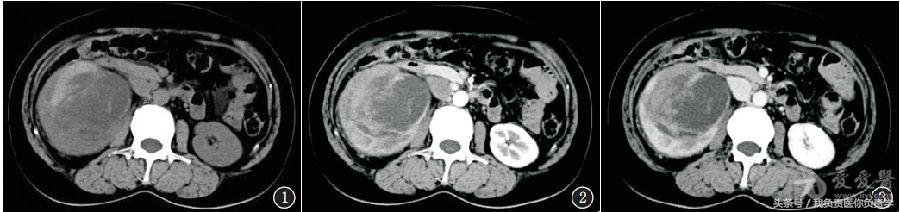

泌尿系CT平扫+增强:右肾见95mm×79mm×94mm囊实性肿块,囊性为主,部分边界清,密度不均匀,内见多发斑片状高密度影,增强扫描实性成分中度不均匀强化,静脉期持续强化,部分集合系统扩张,肾周间隙密度稍增高(图1~3)。腹腔及腹膜后未见肿大淋巴结。

影像诊断:右肾占位性病变并出血,考虑肾盂癌或肾癌。